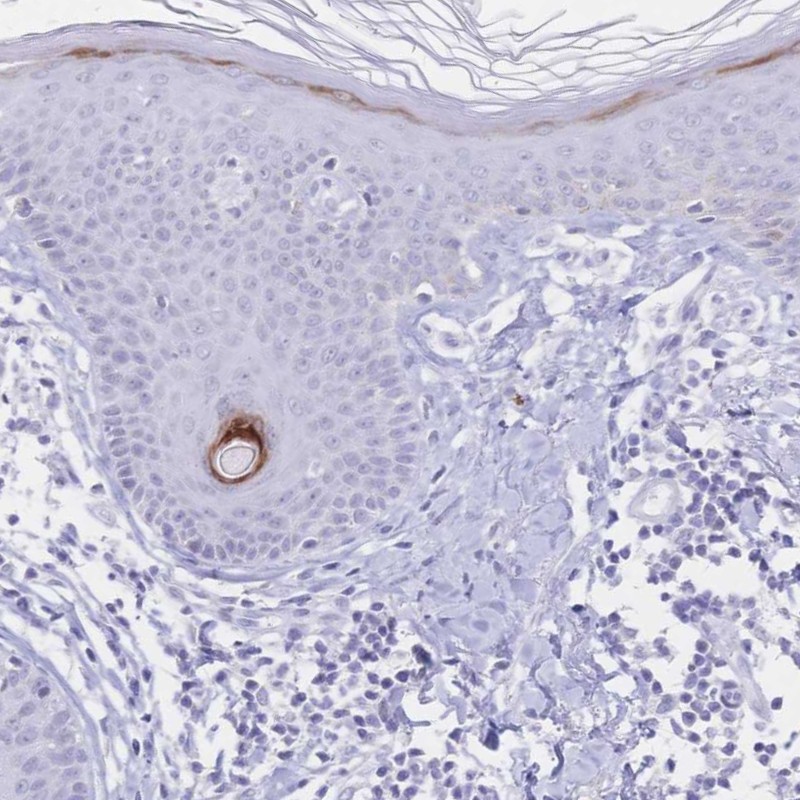

Immunohistochemistry analysis in human skin and skeletal muscle tissues using Anti-PSORS1C2 antibody. Corresponding PSORS1C2 RNA-seq data are presented for the same tissues.